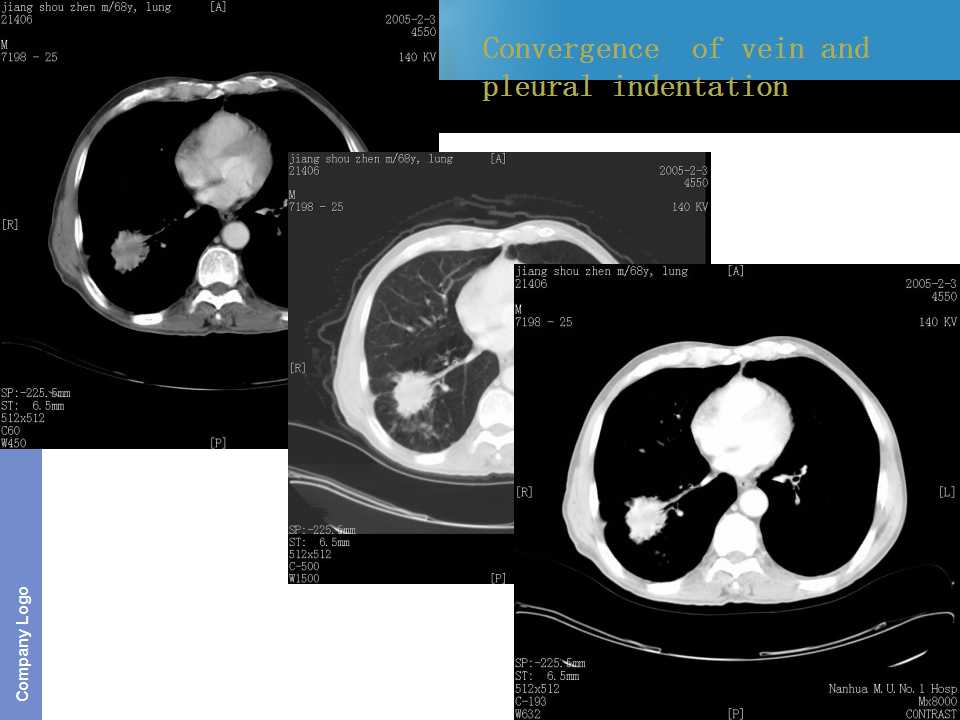

肺癌影像诊断